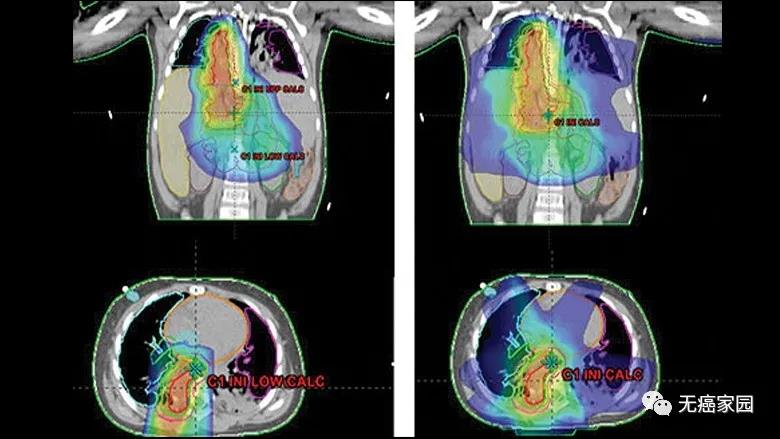

所有患儿在自体干细胞移植治疗后接受质子治疗,26例患儿接受笔形束扫描(PBS)质子治疗,19例接受双散射(DS)质子治疗,其中2例联合X线调强放疗(IMXT);11例患儿接受剂量递增治疗,8例患儿接受转移灶照射。

与X线调强放疗(IMXT)相比,笔形束扫描(PBS)质子治疗具有更优的剂量适形性及靶区覆盖情况。